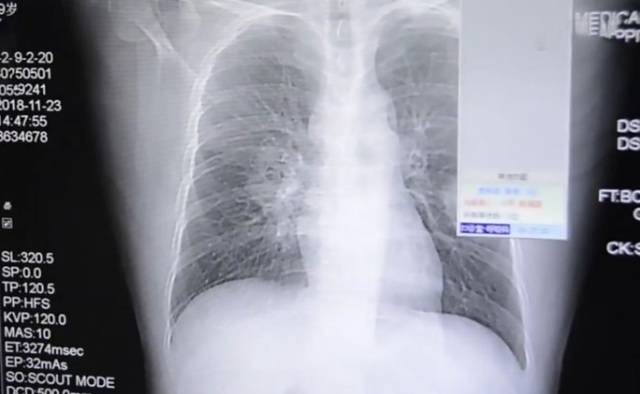

장저우 병원 검진 결과 곰팡이균 감염 폐질환

의료진은 다시 검사한 결과 환자의 폐가 심각한 곰팡이균에 감염돼 있음을 발견했다. 환자를 진료했던 장저우 909병원의 마이 주아닝 의사는 지역언론 복건일보(福建日報)와의 인터뷰에서 "환자가 평소 휴식 부족으로 면역력이 약화돼 곰팡이균에 쉽게 감염됐을 것으로 판단된다"고 말했다.

사이언스 얼러트(Science Alert)는 이 환자가 더러운 양말에서 발견되는 곰팡이 포자를 흡입해 감염됐을 가능성이 크다고 보도했다.

곰팡이균 감염 폐질환은 통상 호흡기관에 영향을 미치지만 그 증상과 심각성은 매우 다르게 나타날 수 있다고 미국 비영리의료기관 메이요 클리닉이 설명했다.